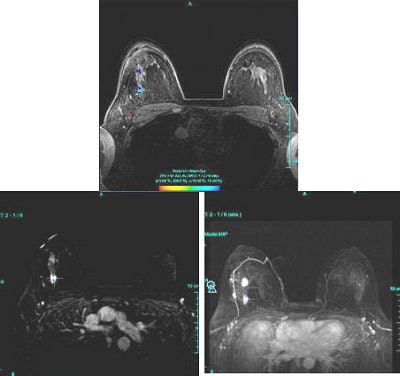

Time-intensity curves were performed with CAD on the right breast lesions at the 10 o'clock position, 3 cm and 4 cm from the nipple (figure 1 and figure 2, respectively, below). Dr. Christiane Kuhl and colleagues described three basic time-intensity curve types as summarized in table 4. A graphic illustration of the various curves is presented in figure 3 (Radiology, April 1999, Vol. 211:1, pp. 101-110).

| Figure 2: Similar type III curve (below) corresponding to the right breast lesion at the 10 o'clock position, 4 cm from the nipple (above). |

Figure 1 demonstrates a type III curve corresponding to the right breast lesion at the 10 o'clock position, 3 cm from the nipple. In observing the parametric map and subtraction image, the enhancement pattern is suspicious for malignancy. A rapid uptake of contrast is immediately followed by rapid washout. Figure 2 shows similar tissue kinetics for the lesion 4 cm from the nipple.